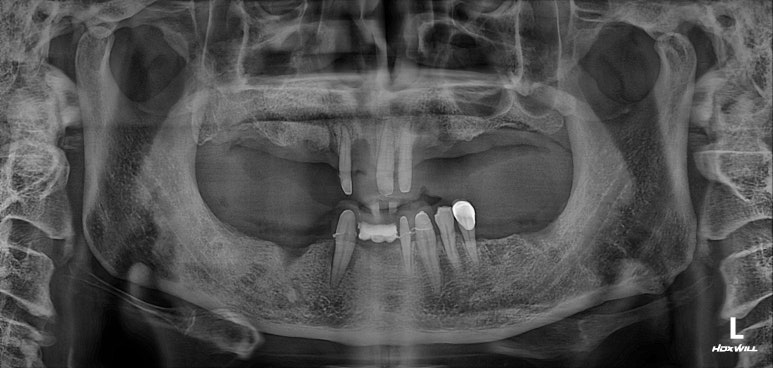

이제 임플란트를 모두 심어내었으니, 3개월 기다려야합니다.

임플란트 2차수술을 하였습니다.

3개월이 지나면, 본인의 잇몸뼈와 임플란트가 단단한 골유착을 형성합니다.

비교적 씹어먹을 수 있게 임플란트가 고정이 되었다는 말씀 !!

잇몸안에 묻혀있는 임플란트를 나중에 머리와 연결할 수 있도록, 통로를 만들어주는 임플란트 2차수술을 시행합니다. 잘 보시면 뭔가 더 길어진 것처럼 보이실거에요~

전체 임플란트 완성!!

제가 개원하고 약 1년 뒤에 시작했던 케이스라 임상 사진이 많이 없네요...